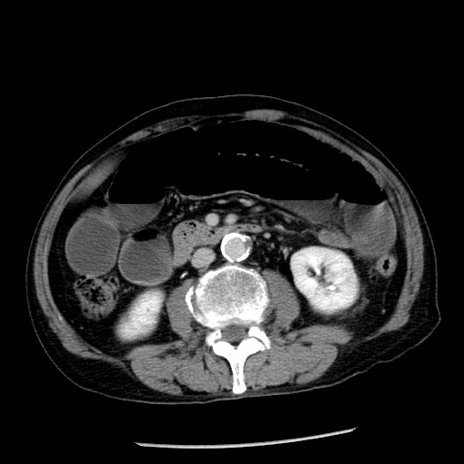

症例26(横断像)

【症例】80歳代男性

【主訴】嘔吐

【現病歴】昨晩2回嘔吐あり、今朝になっても嘔吐あり。来院。

【既往歴】胃潰瘍

【身体所見】意識清明、BT 37.6℃、BP 166/95mmHg、HR 100bpm、SpO2 97%、腹部:平坦・軟、腸蠕動音聴取良好、圧痛なし。

【データ】WBC 21900、CRP 1.46